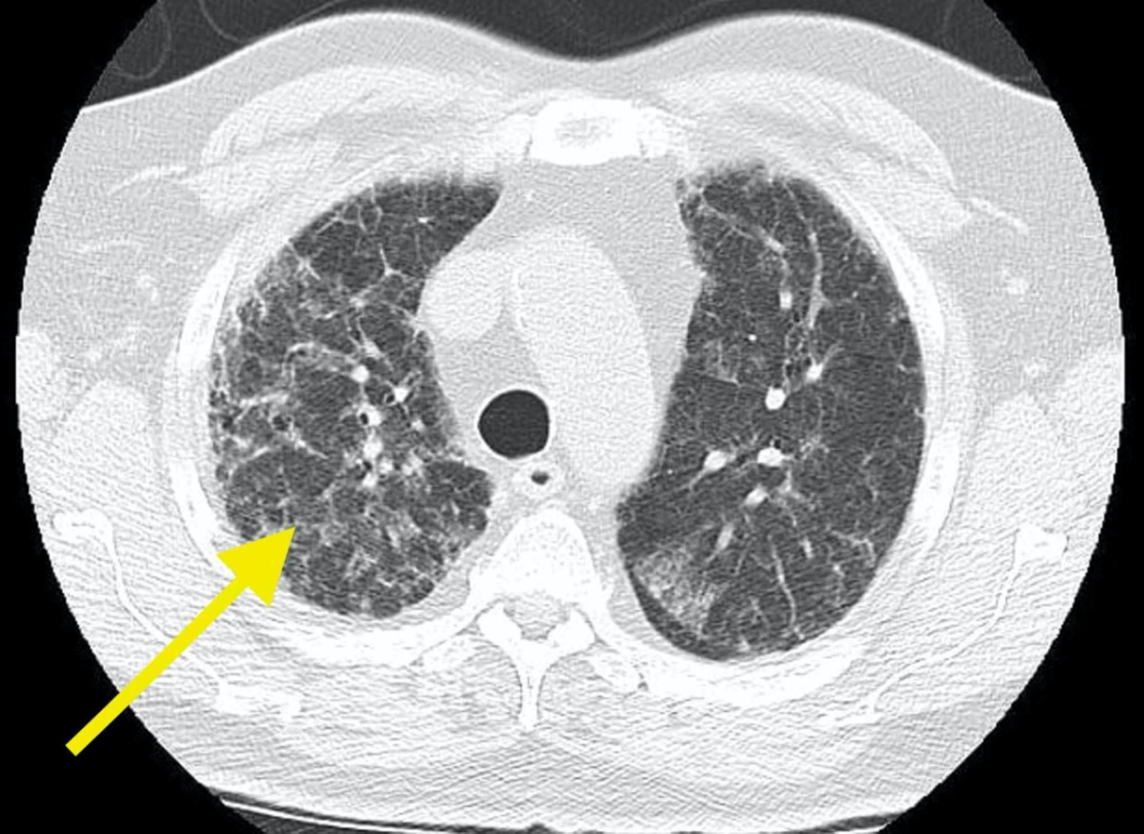

Rx fractura costal

Tórax óseo AP u oblicua

Fractura costal